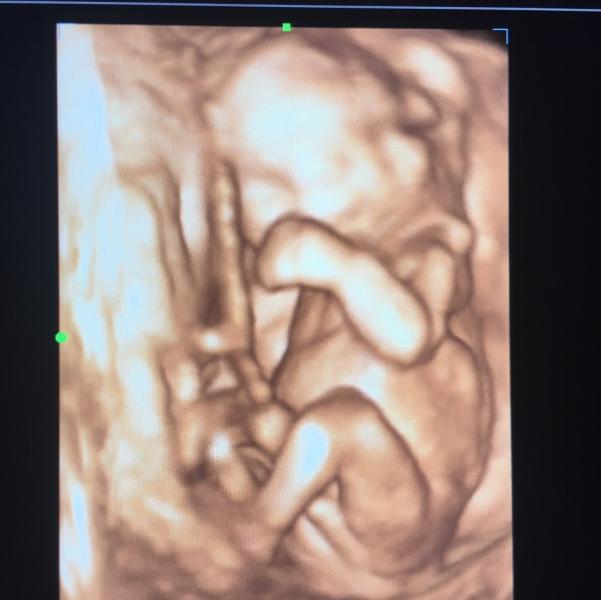

Девочки отправьте пожалуйста узи фото чтоб пол ребёнка видно было 🙏🙏🙏

@aisha_710, ага ☺️на первом узи говорили девочка из за этого хочу сравнить как там между ног бывает хоть 😂